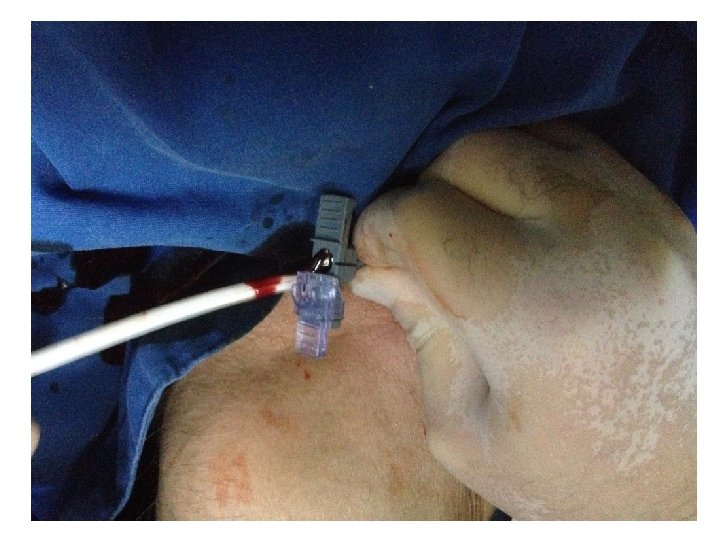

arter yaralanması Sadaf T. Bhutta; Evaluation and Management of Central Venous Access Complications Tech Vasc Interventional Rad 14: 217 -224; 2011